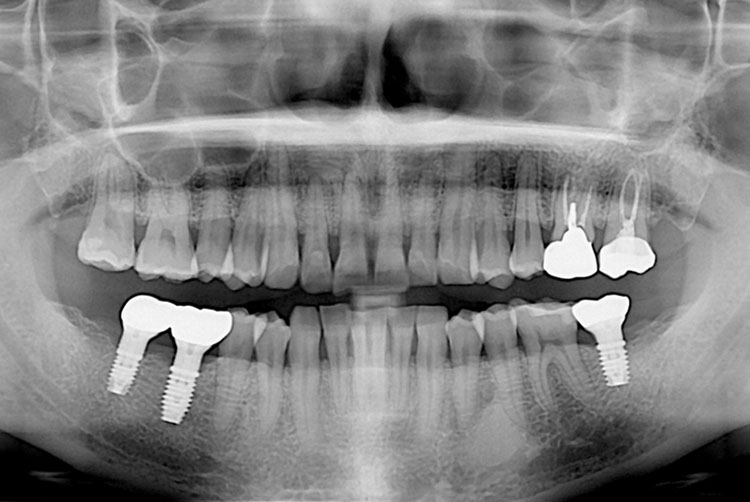

[임플란트] 임플란트

치료후 : 2019-12-20

세종치과는 많은 환자와 다양한 케이스를 바탕으로 항상 편안한 임플란트 수술을 제공하고자 노력하고,

오래동안 튼튼히 쓸 수 있는 임플란트 수술을 가장 큰 목표로 삼고 있습니다